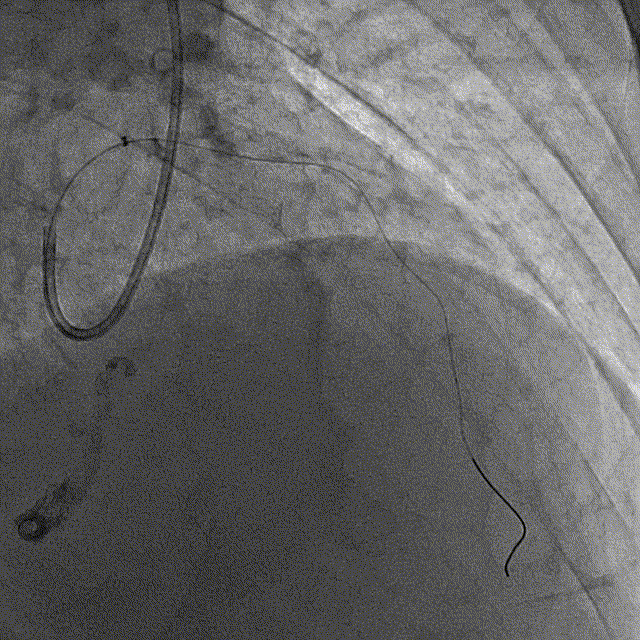

冠脉造影结果:LM外膜钙化,内膜不光滑,中段狭窄90%,TIMI3级。LCX外膜钙化,内膜不光滑,TIMI3级。RCA外膜钙化,内膜不光滑,近段狭窄80%,中段狭窄90%,可见破损斑块,TIMI3级。

冠脉内介入治疗